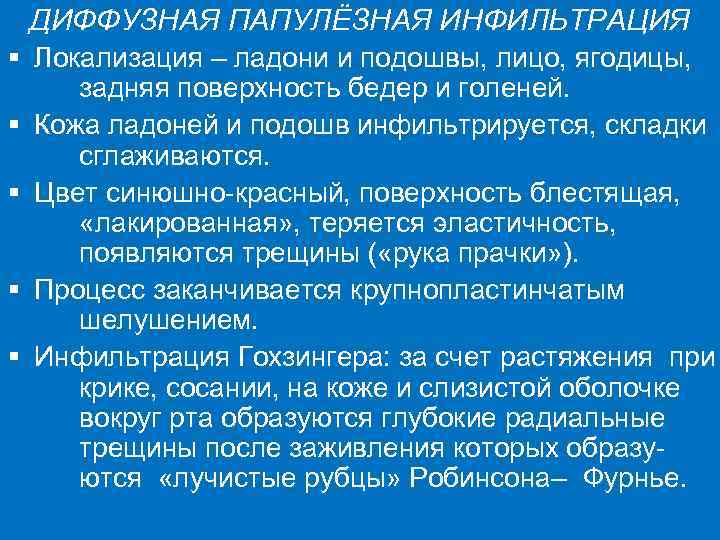

ДИФФУЗНАЯ ПАПУЛЁЗНАЯ ИНФИЛЬТРАЦИЯ § Локализация – ладони и подошвы, лицо, ягодицы, задняя поверхность бедер и голеней. § Кожа ладоней и подошв инфильтрируется, складки сглаживаются. § Цвет синюшно-красный, поверхность блестящая, «лакированная» , теряется эластичность, появляются трещины ( «рука прачки» ). § Процесс заканчивается крупнопластинчатым шелушением. § Инфильтрация Гохзингера: за счет растяжения при крике, сосании, на коже и слизистой оболочке вокруг рта образуются глубокие радиальные трещины после заживления которых образуются «лучистые рубцы» Робинсона– Фурнье.